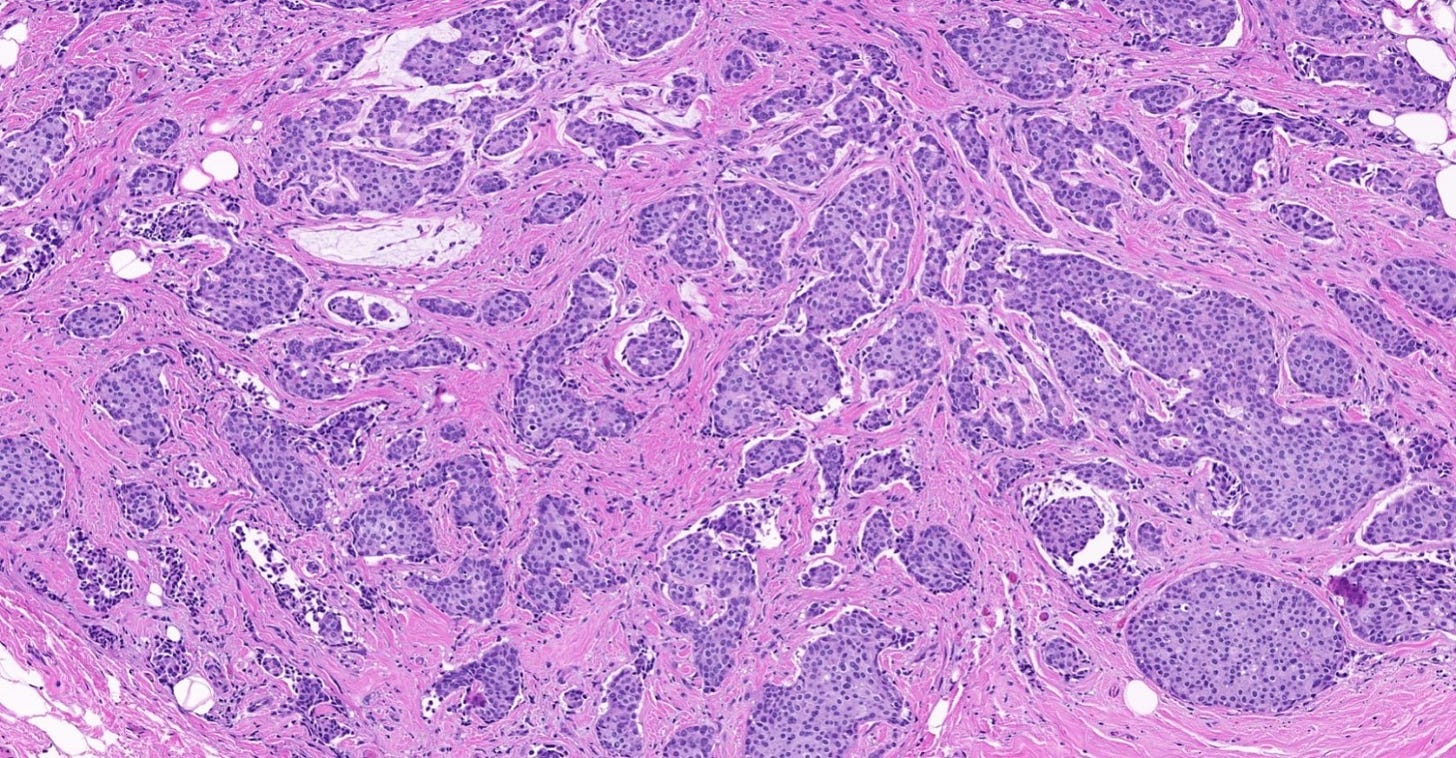

Precursor of classic lobular carcinoma - florid lobular carcinoma in situ

Florid LCIS is a rare (< 5% of LCIS) nonclassical or variant form of lobular carcinoma in situ in which acini and ducts are markedly distended with little to no intervening stroma. It may have a mass-like architecture and includes cells with cytologic features of classic LCIS (type A or type B cells) with or without comedonecrosis and calcifications. Most cases are associated with classic LCIS or atypical lobular hyperplasia (ALH).

Florid LCIS has features of a high risk precursor lesion of invasive carcinoma including a higher upgrade rate, increased association with invasive carcinoma and more genetic complexity compared to classic LCIS.

In contrast to classic LCIS, complete surgical excision of florid LCIS is recommended.

Florid lobular carcinoma in situ - microscopic images